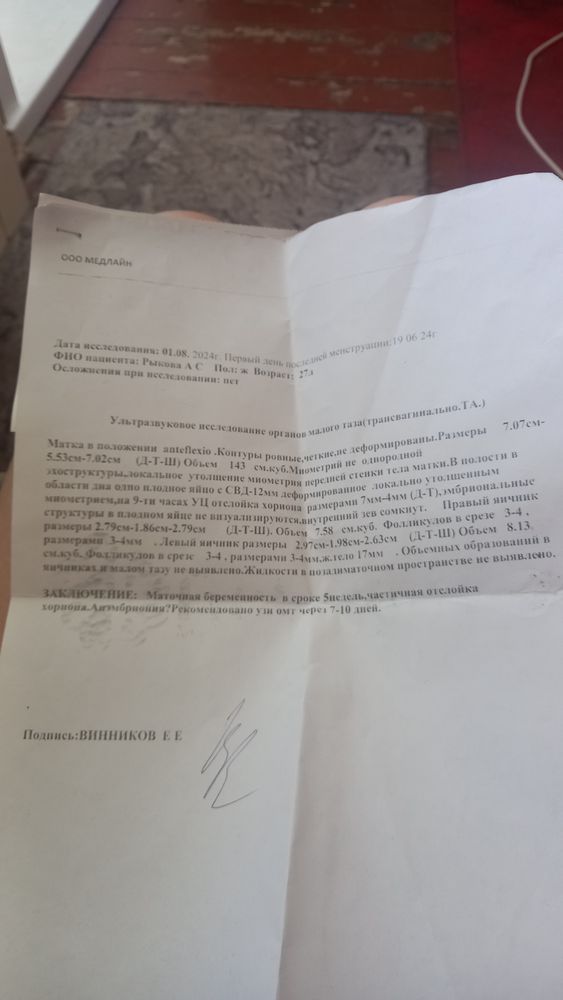

Беременность и узи

Девочки у кого так было чем закончилось?мне по крайней мере кажется что малыш там все таки есть так как на одном из снимков видно креветочку

Элина, спасибо надеюсь все будет хорошо по месячным уже просто седьмая неделя и как гинеколог смотрела по матке такой же срок только по узи 5 недель

Влада , по месячным уже седьмая неделя по тому что гинеколог смотрел тоже седьмая а вот по узи всего пять недель посмотрим что дальше будет завтра к врачу надеюсь все хорошо сыновей двойняшек в 4 5 недель уже было видно

Влада , спасибо огромное но врачи только аборт таблетками предлагают

Влада , я не согласилась в четверг иду на УЗИ надеюсь на самое лучшее